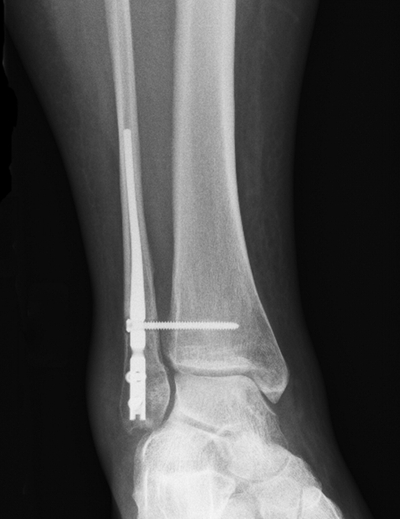

骨折圖片